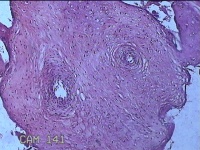

胎盘组织

性别

女

年龄

35岁

临床诊断

胎膜早破 早产

一般病史

停经36+1周,阴道流液3天。

标本名称

大体所见

灰白暗红色胎盘组织18x15.5x2.3㎝一个,表面光滑,血管清晰,颜色发暗,绒毛面结节状,轻度糜烂,表面有少许凝血块,切面见绒毛内有部分淤血,边缘蜕膜可见多个小血肿,脐带15x1.5x0.8㎝,切断脐带,见脐血管内有凝血块。